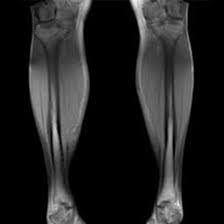

Specific Body MRIs

Get a specific body, organ, looked at with advanced MRI imaging

Partial body MRI for scanning of places such as abdomen, chest, or head.